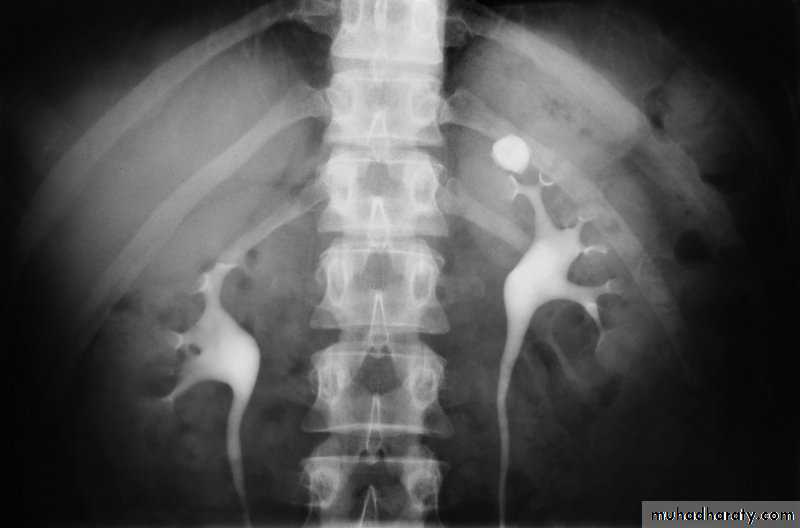

l.V.U. findings:

-Plain film may be useful in demonstrating calculi. -After contrast injection: Acutely obstructed kidney shows a dense nephrogram (dense opacification of the renal parenchyma).

excretion of contrast (opacification of the collecting system which may take many hours) ,

then the level and degree of obstruction can be determined as dilated pelvi-caliceal system and ureter are followed down to the point of obstruction (point of hold up).

-Principal feature is dilatation of the pelvicalyceal system and ureter.

• The dilatation is down to the level of pathology